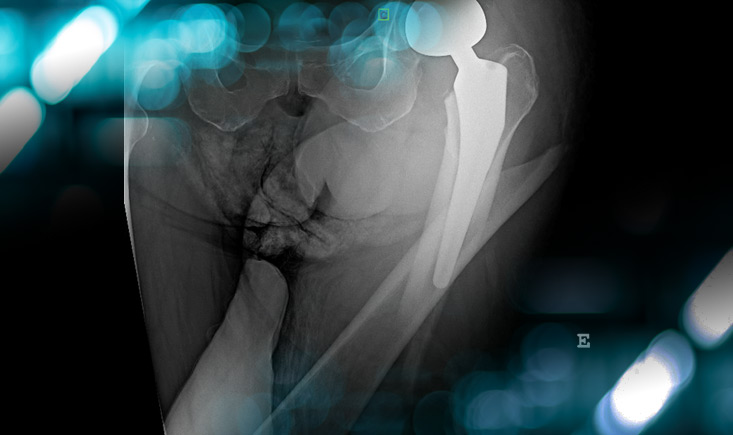

Final strategy decision

• In this case, we decided to perform a simple ORIF with a plate (Depuy Synthes) due to the Vancouver B1 type of fracture and Remaining Attachment Index >  2/3

• A full weight bearing was allowed because of her condition.

• At 6 weeks post-op she was able to walk with her walker again

Postoperative imagery